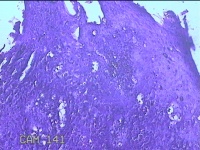

尿道口肿物

性别

男

年龄

46岁

临床诊断

尿道肿物

一般病史

发现尿道口肿物10余天。

标本名称

大体所见

灰白粉红色不规则肿物0.8x0.5x0.2一堆。

似有挖空细胞,有可能要考虑湿疣,片子这个效果,真是不敢猜。